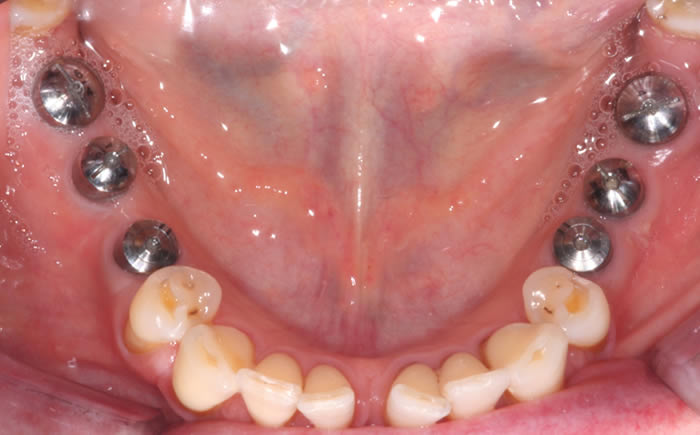

Six missing lower back teeth replaced by dental implants

Full arches of teeth replaced by dental implants

Case One (5 images)

Full set of lower teeth fixed onto five dental implants.

Case Two (8 images)